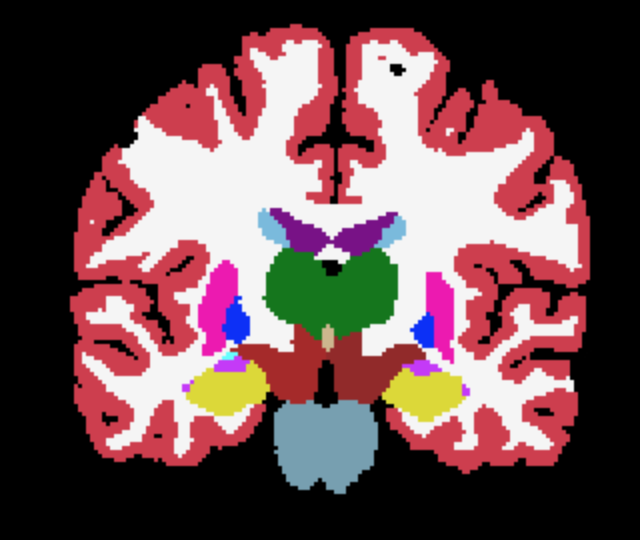

We can further propagate the uncertainty of the transformation to downstream tasks. As an example, we used registration-based segmentation. Given that we can draw samples of the spatial transformation, we can propagate multiple versions of an atlas segmentation (see Figure 1). Each sample from the transformation leads to one possible segmentation map, resulting in different versions of segmentation maps, which can be used to estimate a distribution of labels at every spatial location – and derive its uncertainty using, e.g., the entropy of this distribution. We call this the third level of uncertainty.

where and are the ground-truth and transformed segmentations respectively, and the Dice loss is now computed over multiple neuroanatomical structures (see Figure 1 for an example segmentation).

The overall training framework of the network is illustrated in Figure 1. Given an input scan, the network regresses both the coordinate means and the standard deviations , as well as a foreground mask . The optional atlas segmentation loss is denoted by the dashed box.

Third-level uncertainty: uncertainty at downstream tasks. To illustrate how the uncertainty could be used in a downstream task we show samples of atlas deformations and associated propagated segmentations in Figures 5 and 6. Both figures highlight the variability of the samples, which would have a direct effect on any downstream analysis using quantities extracted from the segmentations, e.g., regional volume (Desikan et al., 2009). The sample-to-sample differences, along with the variance, are again concentrated on the cortex. This registration-based uncertainty, when not accounted for, can decrease the power of downstream statistical analyses, or be mistaken for aging effects if the registration errors correlate with age.